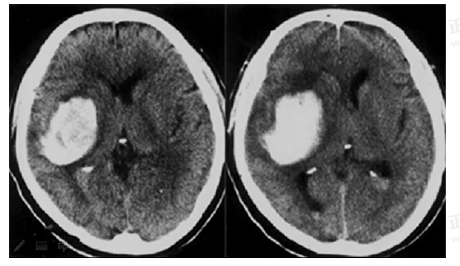

試題2:男,44歲。頭部外傷12小時(shí)。結(jié)合CT片,此診斷為(2分)

A.硬膜下血腫

B.腦出血

C.硬膜外血腫

D.顱骨骨折

E.腦血栓

答案:C

影像學(xué)2